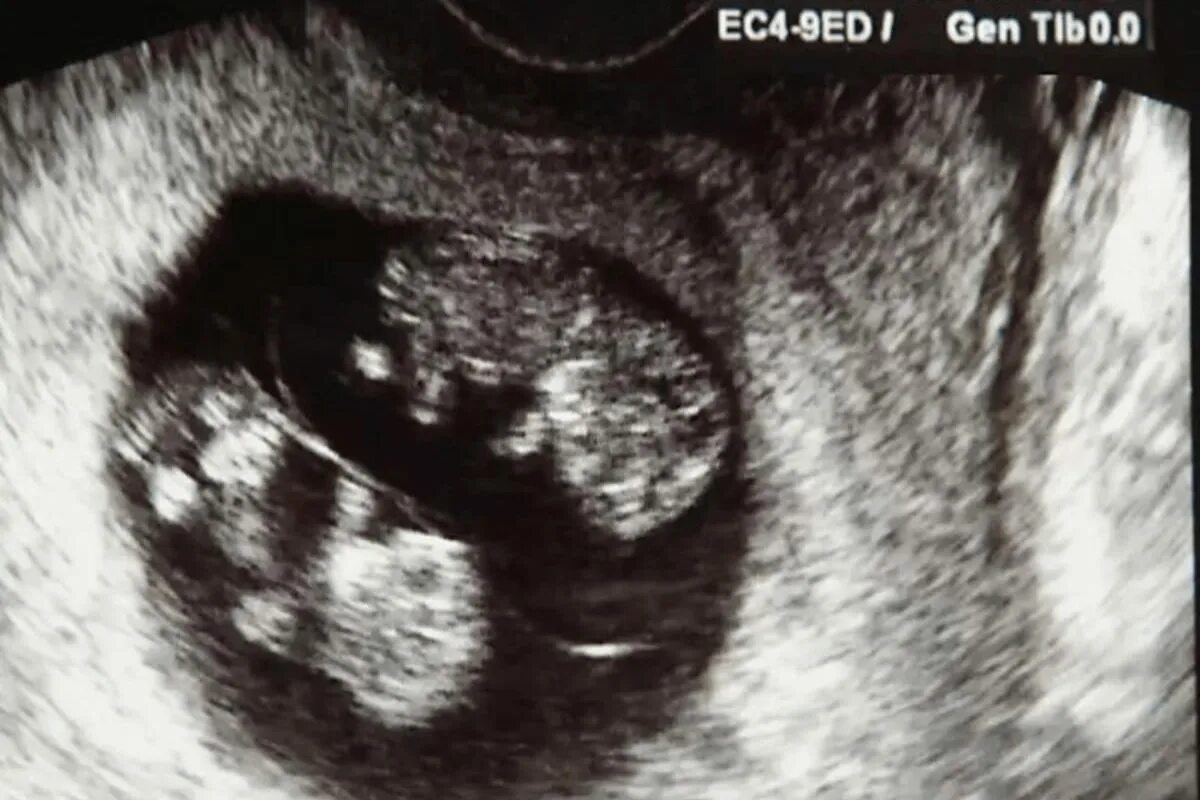

Узи 6 месяцев